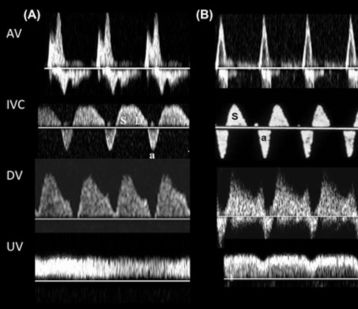

Multivessel color Doppler

This technique measures blood flow in the umbilical cord, fetal heart, and other blood vessels. It is used to evaluate the health of the placenta and assess potential complications such as fetal growth restriction.